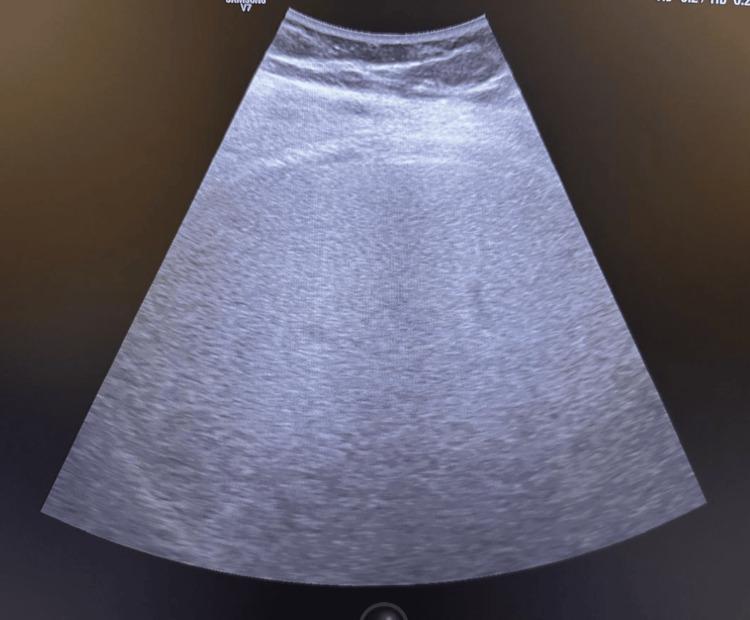

Semaglutide (Ozempic), a Glucagon-like peptide-1 (GLP-1) receptor agonist, has shown promise in improving glycemic control and offering renal protection in type 2 diabetes. We present the case of a 40-year-old male with poorly controlled type 2 diabetes and early diabetic nephropathy, who experienced significant metabolic and renal improvements following semaglutide therapy. Initially, on SGLT2 inhibitors, the patient discontinued treatment due to recurrent urinary tract infections. On presentation, he exhibited hyperglycemia, dyslipidemia, proteinuria, and reduced eGFR. Semaglutide was initiated alongside metformin, gliclazide, antihypertensives, and lipid-lowering agents. Over 12 months, HbA1c improved from 9.8% to 6.1%, and urine albumin-to-creatinine ratio decreased from 267 mg/g to 34 mg/g, with improved eGFR. This case supports the renoprotective and metabolic benefits of semaglutide and highlights its potential as a therapeutic option in patients intolerant to SGLT2 inhibitors.

司美格鲁肽(Ozempic)是一种胰高血糖素样肽-1(GLP-1)受体激动剂,已显示出在改善2型糖尿病患者血糖控制及提供肾脏保护方面的前景。我们报告一例40岁男性2型糖尿病控制不佳且患有早期糖尿病肾病患者,其在接受司美格鲁肽治疗后代谢及肾脏状况有显著改善。最初,该患者使用钠-葡萄糖协同转运蛋白2(SGLT2)抑制剂时,因反复发生尿路感染而停药。初诊时,他表现为高血糖、血脂异常、蛋白尿及估算肾小球滤过率(eGFR)降低。遂开始使用司美格鲁肽,同时联用二甲双胍、格列齐特、抗高血压药及降脂药。在12个月的时间里,糖化血红蛋白(HbA1c)从9.8%降至6.1%,尿白蛋白与肌酐比值从267mg/g降至34mg/g,eGFR有所改善。该病例支持司美格鲁肽具有肾脏保护及代谢益处,并突出了其在不耐受SGLT2抑制剂的患者中作为一种治疗选择的潜力。